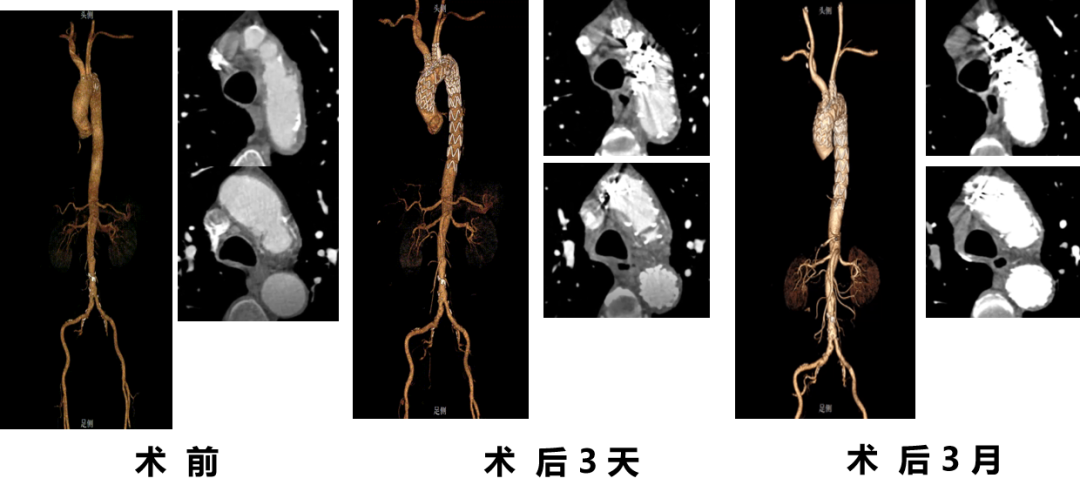

韩某,男,53岁,“查体发现主动脉弓部溃疡15天”入院,主动脉CTA提示:主动脉溃疡(弓部);2. 主动脉壁内血肿。患者高血压病史8年,最高210/130mmHg,无规律服药。

术前 CTA

术前

术后

手术用时115分钟